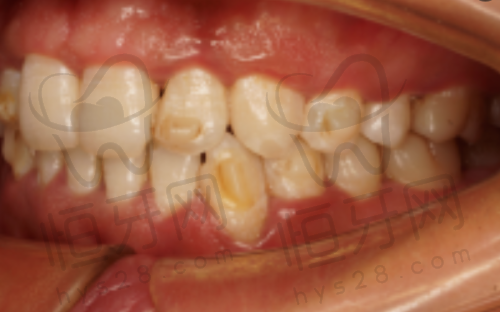

对于青少年矫正,医院还有孙明珠医师这样的骨干医生,擅长早期干预治疗。北京劲松口腔医院的正畸特色是"量齿定制",会根据每个人的牙齿情况制定专属方案。特别多患者反馈矫正成效超出预期,连脸型都变好看了呢!

带孩子看牙再也不用"斗智斗勇"啦!北京劲松口腔医院的儿童牙科团队超级贴心。郭红芳医师有14年经验,擅长儿童舒适化治疗,让孩子在轻松环境中完成治疗。孙明珠医师则精通各种儿童早期矫治技术,能预防和纠正地包天等问题。